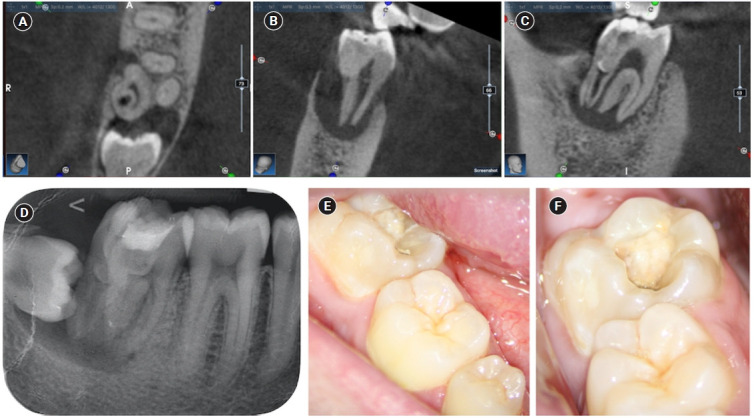

本病例报告描述了三根下颌第二磨牙的III型B齿内陷(DI)的根管治疗,因为内陷侵入根并延伸到根尖。下颌第二磨牙的临床和锥形束计算机断层检查显示冠状形态变宽,DI,第三根,根尖周放射率,内陷压迫远端根管,形成非典型的半月形。诊断为牙髓坏死,有症状的根尖和牙周炎。因此,进行三维虚拟重建,以改善解剖解释和病例规划,并通过减少操作员压力和最小化术中变量来加快术中阶段。本病例报告旨在提高人们对下颌第二磨牙DI存在的认识。

The present case report describes the endodontic treatment of a type III B dens invaginatus (DI) in a three-rooted mandibular second molar since the invagination invades the root and extends apically. Clinical and cone-beam computed tomography examination of the mandibular second molar showed a broadened coronal morphology, DI, a third root, periapical radiolucency, and compression of a distal root canal by the invagination, which developed an atypical semilunar shape. The tooth was diagnosed with pulpal necrosis, symptomatic apical, and peri-invagination periodontitis. Consequently, three-dimensional virtual reconstruction was conducted to improve anatomical interpretation and case planning and accelerate the intraoperative phase by reducing operator stress and minimizing intraoperative variables. The present case report aims to raise awareness of the existence of DI on the mandibular second molar.